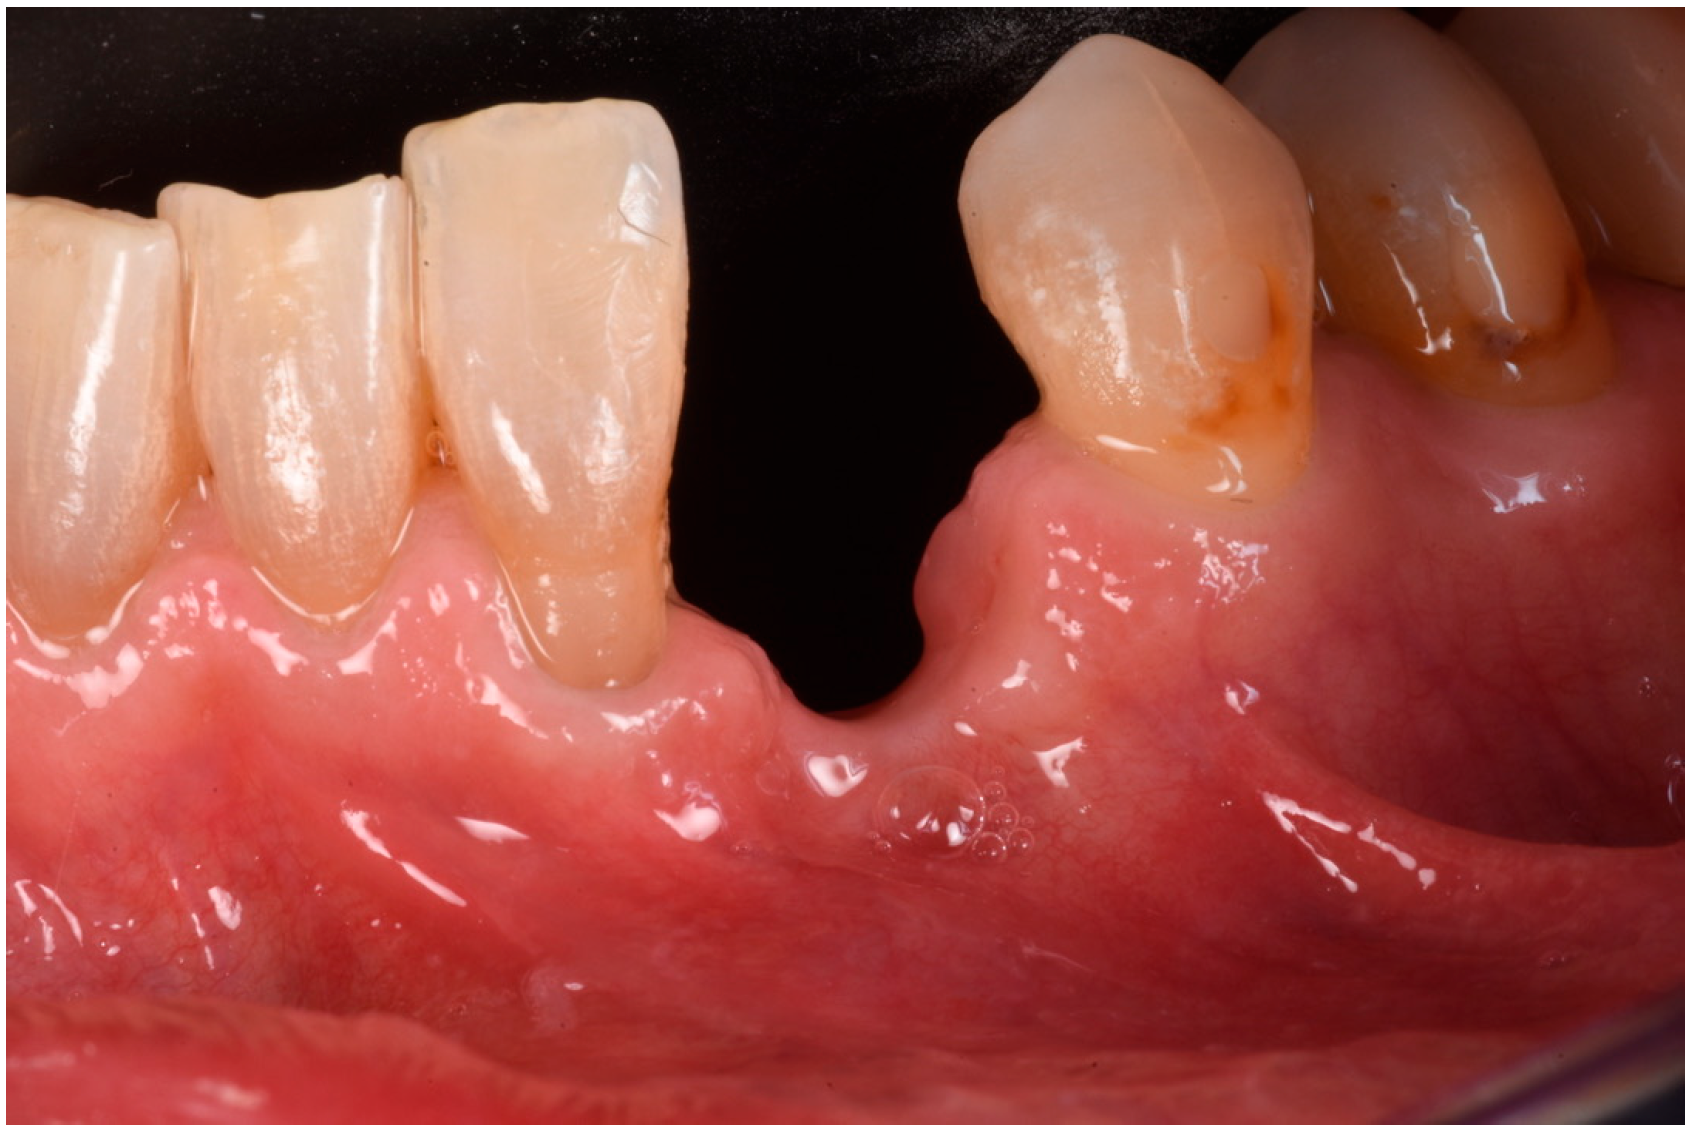

3.3. Implant Insertion and Follow-Up

On the day of surgical re-entry for implant insertion, the area was anesthetized with articaine 1:200,000, and full-thickness flaps were elevated to expose the surgical site. Clinically, newly formed bone and the two FCSs that had fully integrated into the local anatomy were observed. A trephine with a 4 mm inner diameter was used to collect a biopsy from the area for histological analysis. A 4.5 mm × 13 mm implant (Institute Straumann, Basel, Switzerland) was placed at the site. Given that the implant stability quotient (ISQ) measured above 70, a healing abutment was also placed, and the soft tissue was sutured around it. Two months post-implant placement, the healing of the soft tissues was uneventful. A temporary crown was then placed to condition the soft tissue at the site (Figure 13).

After three uneventful months, the final impression was taken, and a zirconia restoration was secured in position. The pictures and radiographs taken at the 18-month follow-up showed perfect stability of the soft and hard tissue complex (Figure 14). A summary of the procedure is provided in Figure 15a,b.

Figure 13. The sequence of biopsy, implant insertion, and healing.

Figure 14. Eighteen-month follow-up after implant rehabilitation, demonstrating optimal maintenance of soft tissues.